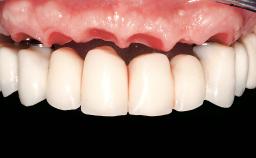

In this case, Arndt Happe describes how he achieved a stable outcome at 5 years by giving careful attention to the coronal aspect of the transmucosal area of the provisional, creating a slim emergence profile.